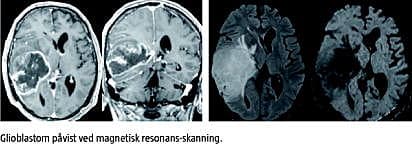

Resultaterne er præsenteret i årsrapporter som er tilgængelige via [2]. Her kan man også se specifikation af de syv indikatorer. Disse omhandler overlevelse hos patienter med glioblastom, udførelse af postoperativ magnetisk resonans (MR)-skanning, om operationen er udført med speciallægekompetence, om der er resttumor efter operationen hos patienter med glioblastom, overlevelse 30 dage efter operationen, postoperativ strålebehandling og postoperativ kemoterapi til patienter med glioblastom. DNOR har udgivet sin fjerde årsrapport [2].